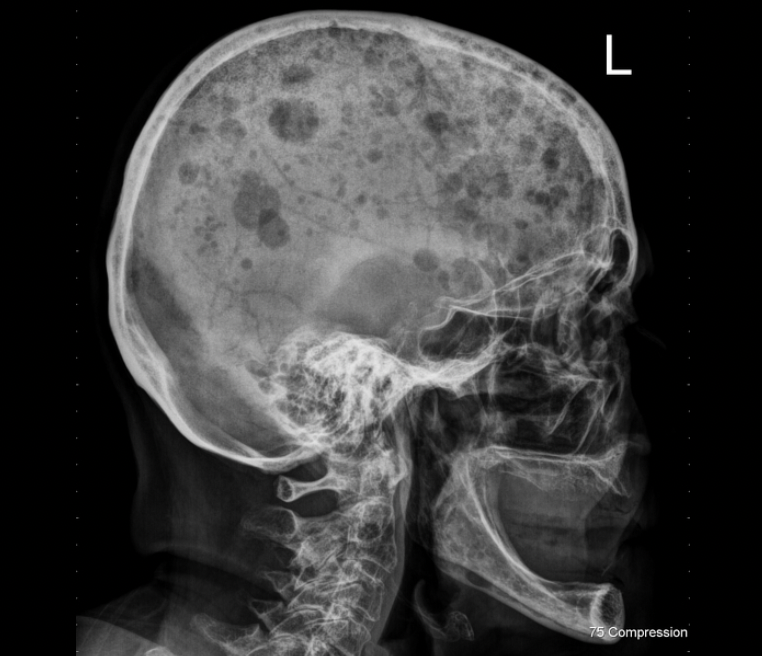

What is the best diagnosis for the pano below?

A

static bone cyst